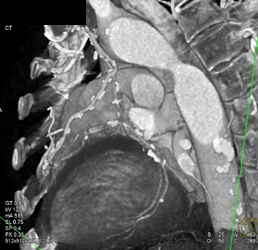

Patent Bypass Grafts